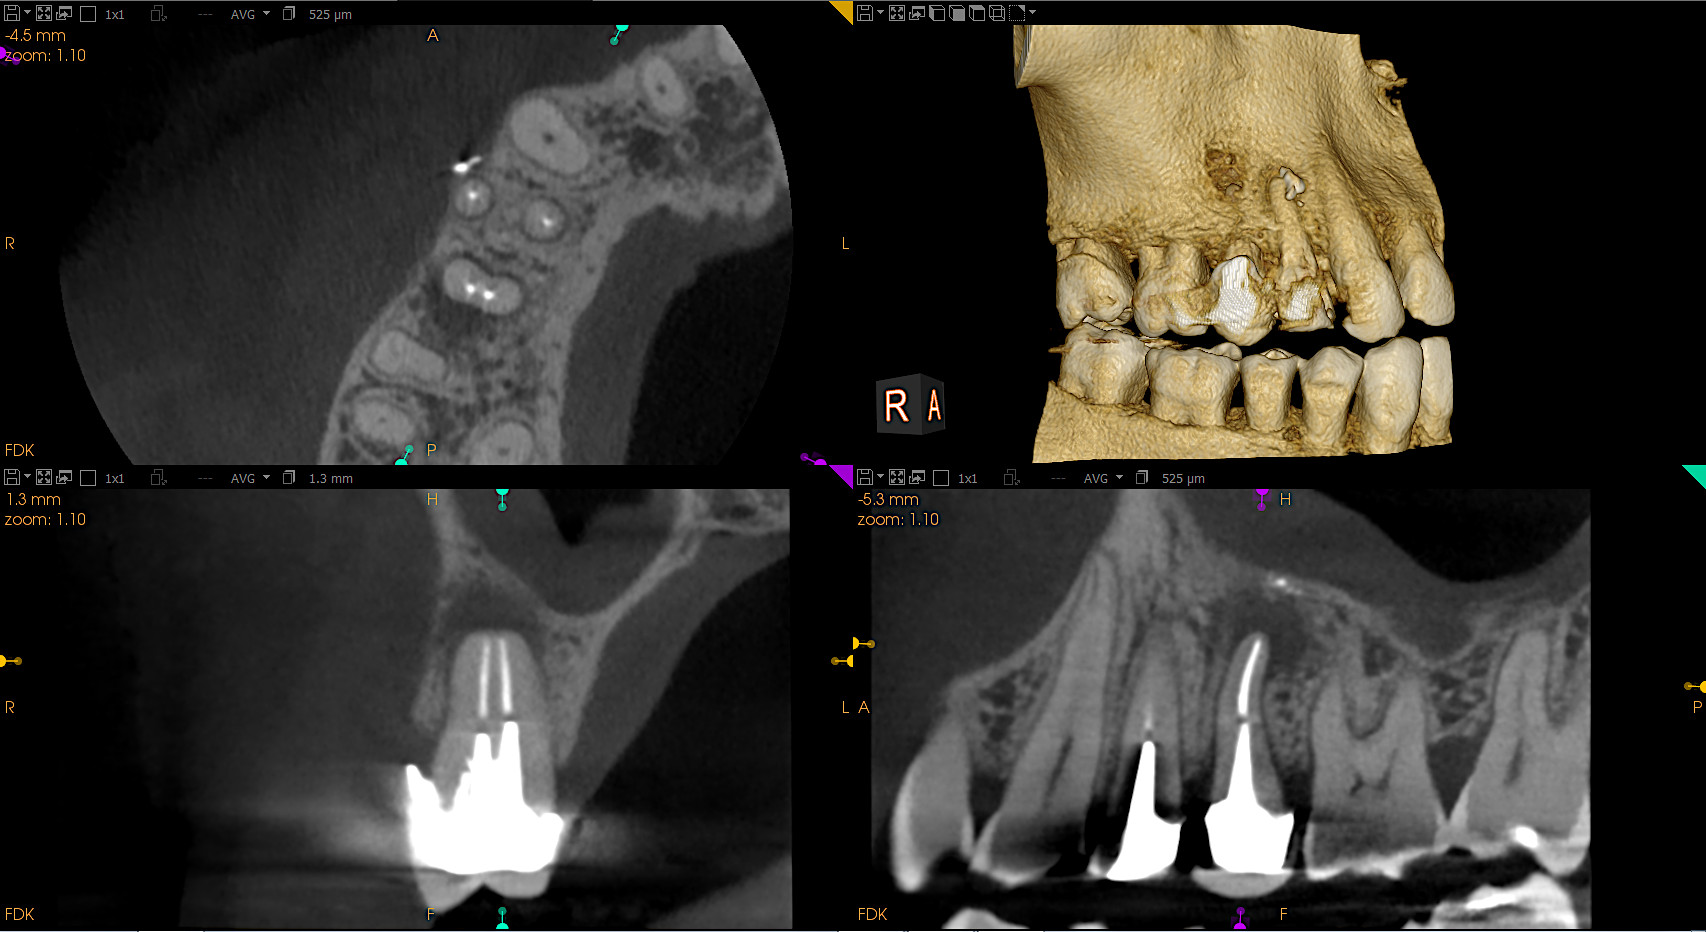

CS 9600 CBCT

S novim Scan Ceph modulom i drugim inovacijama, najinteligentniji CBCT sustav na svijetu sada je još pametniji i svestraniji nego ikad. Sustav redefinira kvalitetu i upotrebljivost, što ga čini savršenim sustavom snimanja za stomatologe i specijaliste koji žele novu razinu preciznosti.

Kristalno jasne slike s ograničenim artefaktima i šumom